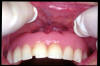

CM Hiperplasia gingival por prótesis